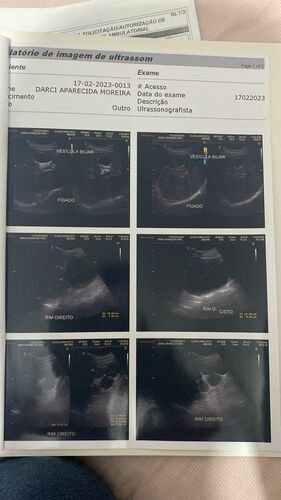

Meu nome é Bruna criei está vaquinha no intuito de ajudar minha tia Darcy que no momento não tem condições de pagar por uma tomografia que ela necessita fazer com urgência, por motivo do qual através de ultrassom e exames não conseguir descobrir o real motivo te tantas dores fortes que vem sentindo e as idas de várias vezes ao pronto socorro por dor. E pelo SUS não faz a tomografia que ela necessita como podem ver no exames o médico pede com urgência…. Agradeço desde já que Deus abençoe a todos que contribuírem..